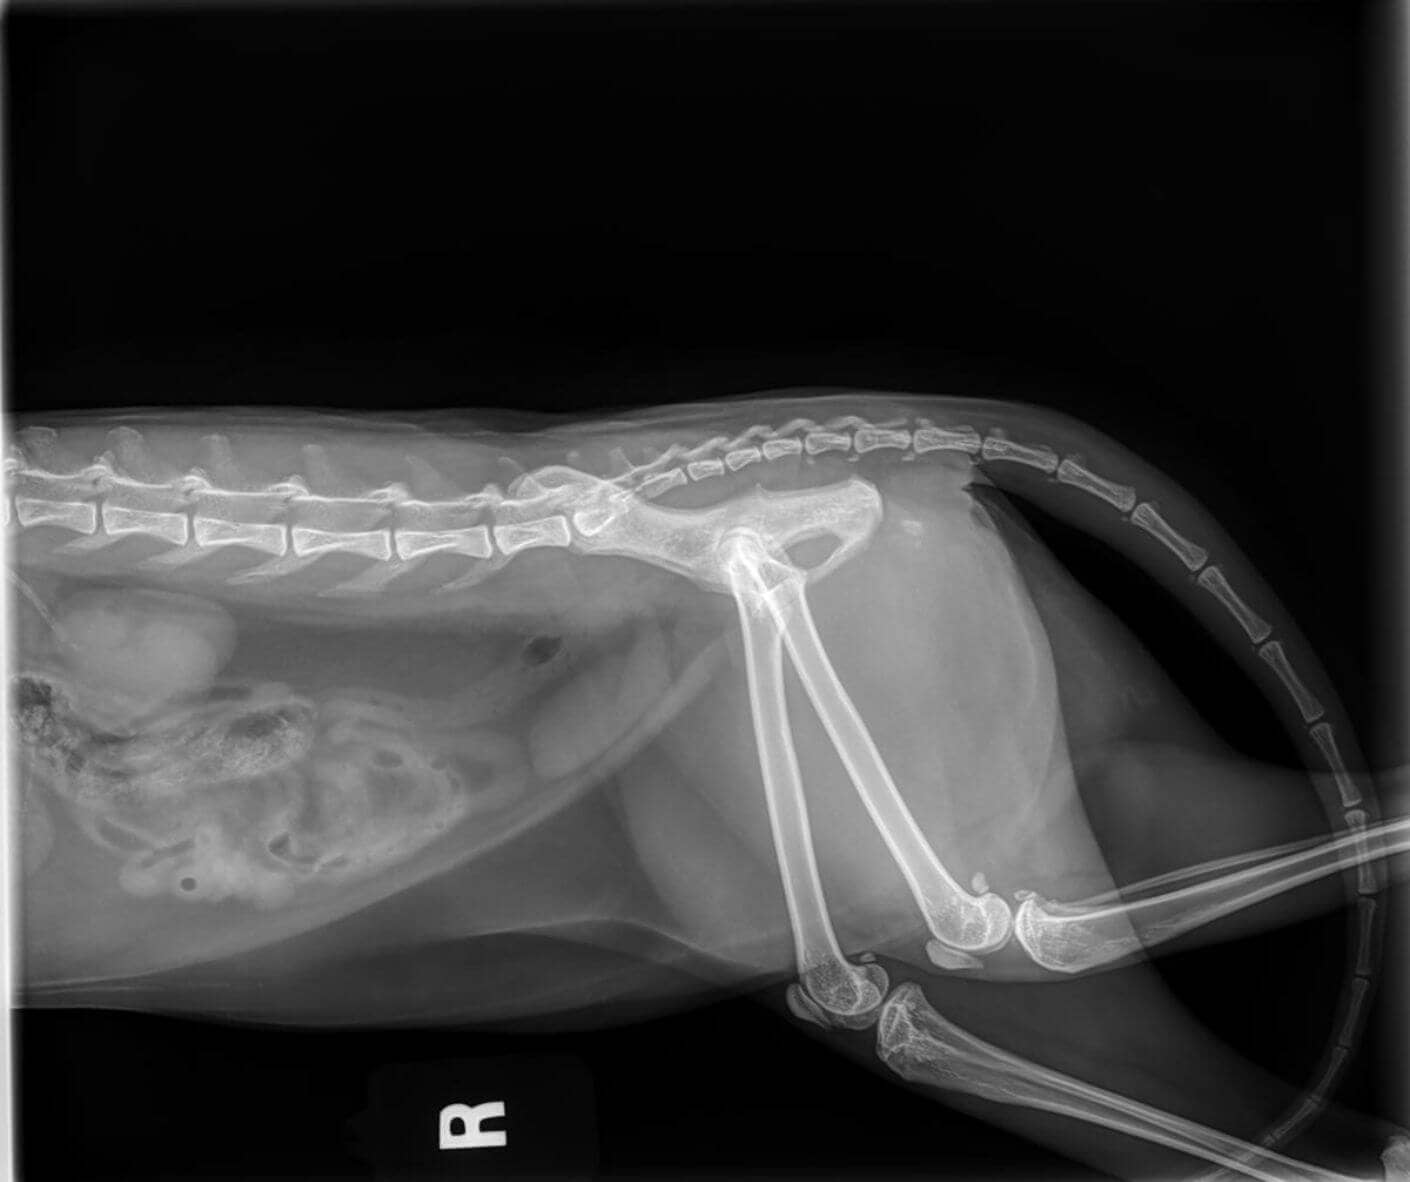

• Major trauma (e.g. fall, car accident, bite wound)